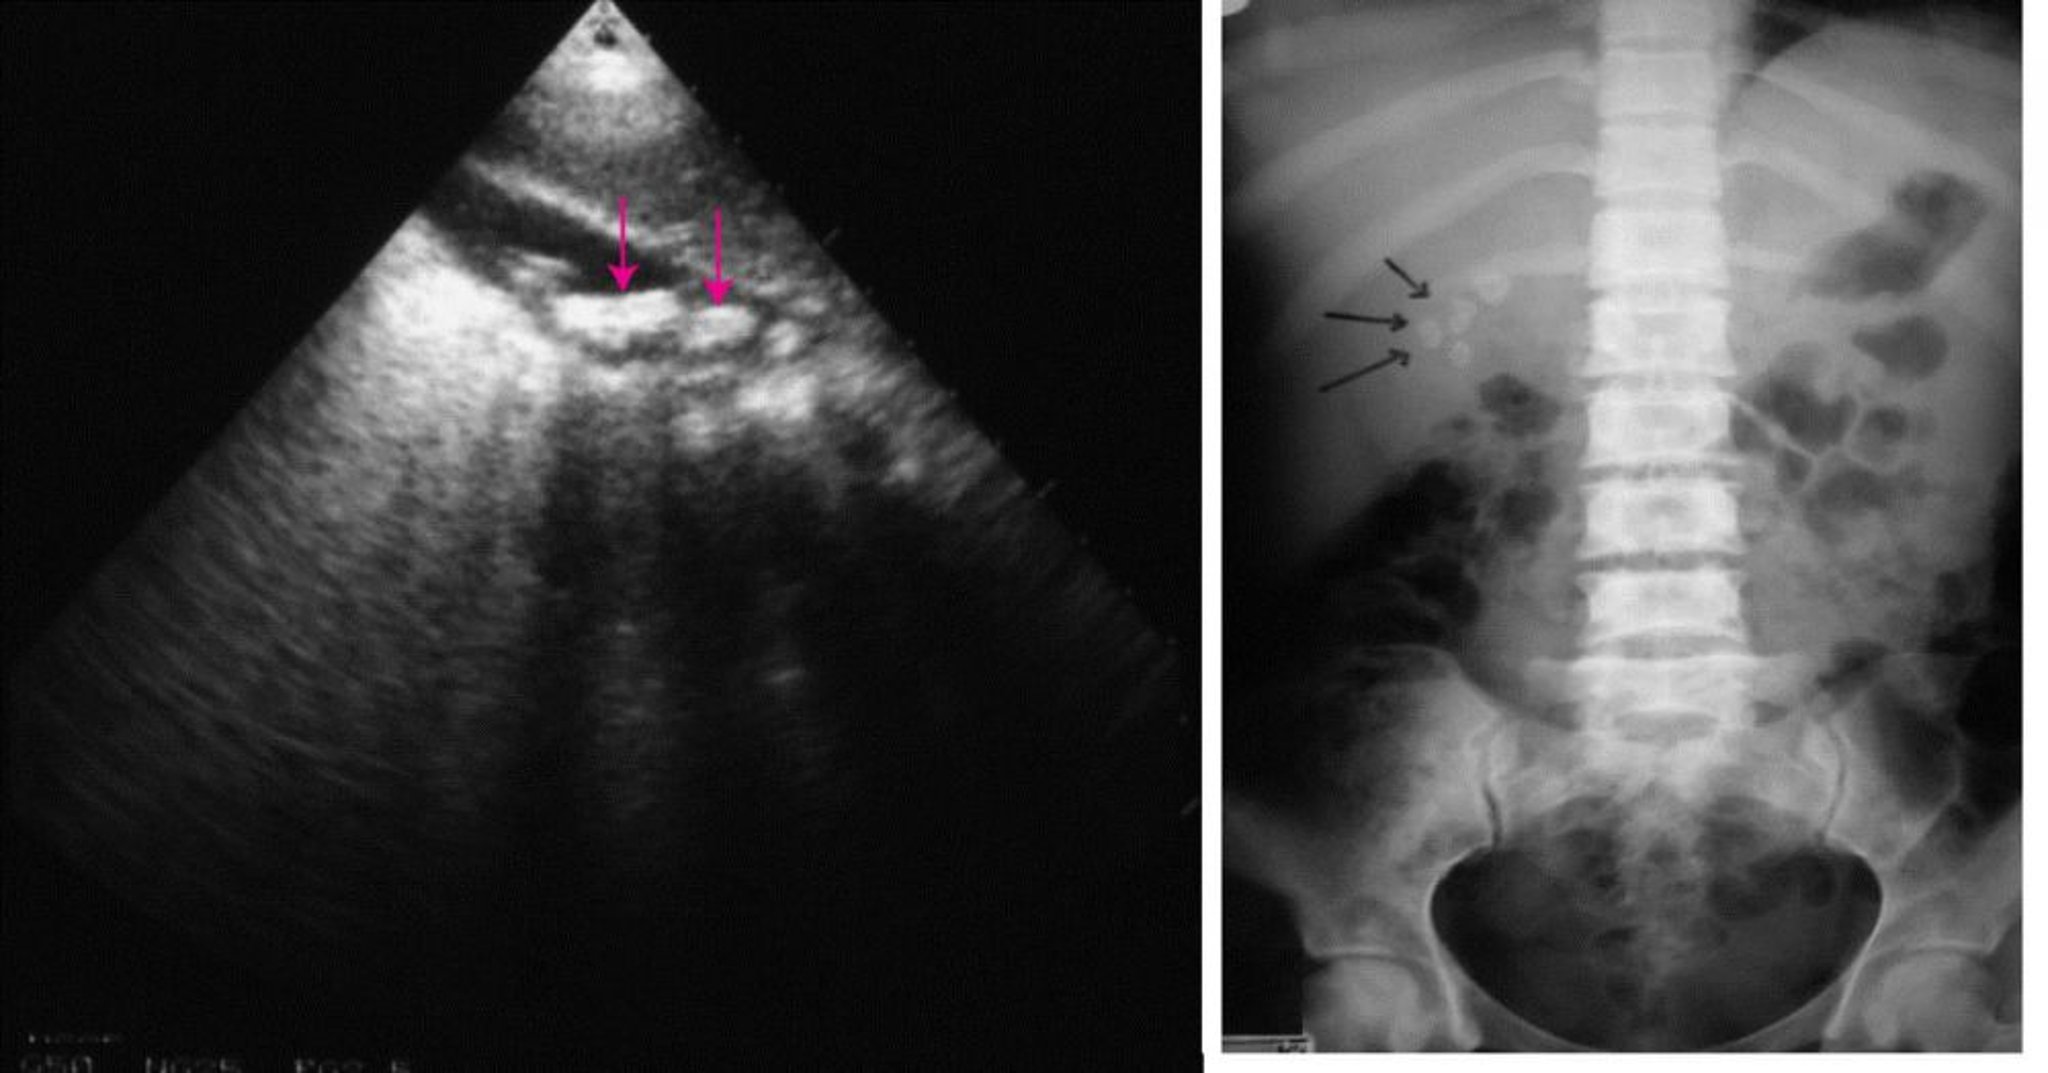

Imagerie abdominale (calculs biliaires)

À gauche, une échographie abdominale montrant plusieurs calculs biliaires (flèches). À droite, une radiographie abdominale sans préparation montrant des calculs biliaires radio-opaques (flèches).